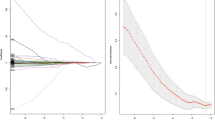

Radiomic feature selection

After the reproducibility analysis, 283 and 173 features were included for arterial and portal venous phase CT images separately. The distributions of the radiomic feature reproducibility in both phases are presented in Supplementary Fig. S2. Next, 205 and 82 features in the two phases were found to be significantly related to grade with a univariable analysis. The results of mean AUCs with 100 times fivefold cross-validation in the RF classifier and feature numbers are shown in Fig. 3. It can be inferred from the curves that the RF classifier obtained the best discrimination performance with 15 and 10 features in the arterial and portal venous phases respectively. The number of radiomic features after these feature selection methods is described in Table 2. All of the selected features of the double phases and predictive performance in the training and validation cohorts are shown in Supplementary Table S2.

The mean AUC for 100 times the fivefold cross-validation in the random forest classifier constructed with different feature subset sizes. The optimal feature subset sizes for the arterial and portal venous phases were 15 and 10 with the best cross-validation AUC of 0.795 and 0.684 in the training cohort